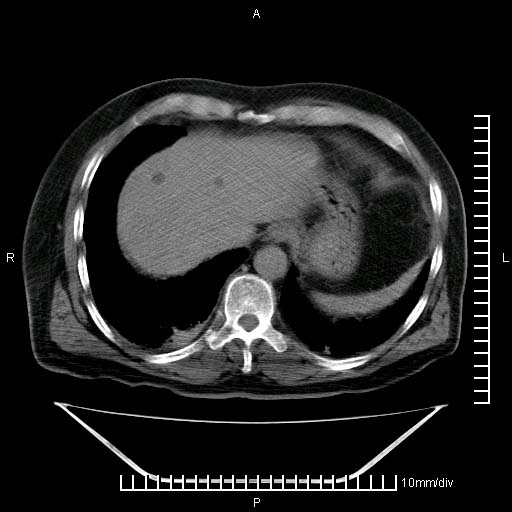

标题: CT25082:肝脏增强:男性,70岁 [打印本页]

标题: CT25082:肝脏增强:男性,70岁

患者以心脏疾病收住院,腹部无明显症状,b超查肝脏有占位。

牛眼征,中心坏死无强化,外缘强化,最外缘又见低密度,考虑转移,与脓肿鉴别

肝内多发转移瘤,右下肺炎症并少量胸水。胃壁增厚建议胃镜,胰尾部“病变”为肠管。

1)肝脏多发性转移瘤(不排除胰尾癌转移所致可能)。2)腹水。3)右侧少量胸腔积液。

ct25082 结果:转移瘤

外院mr结果:胰尾恶性占位。

肝多发低密度灶;轻度强化,较水密度高,考虑转移,不排除肝脓肿